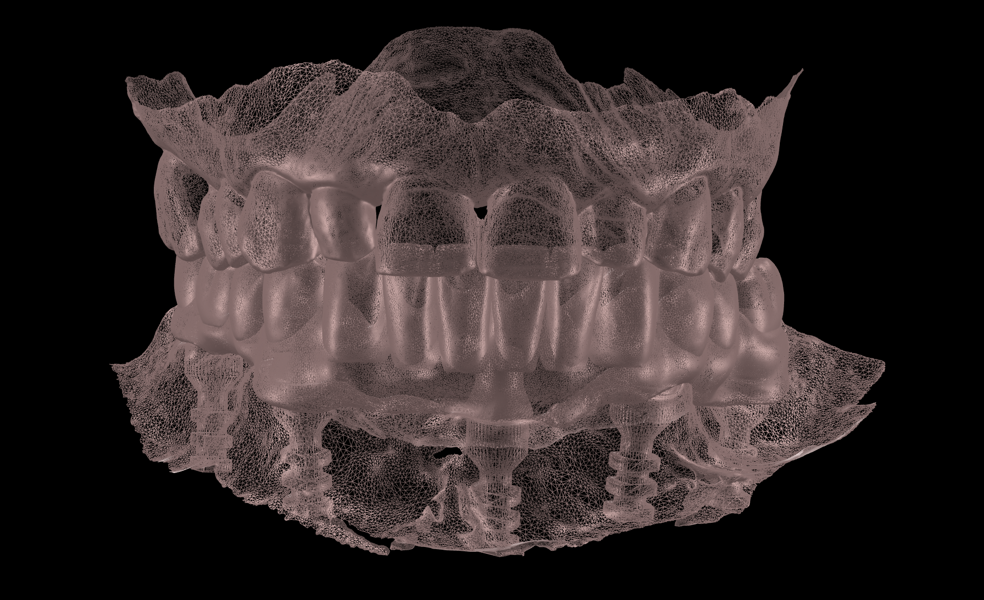

Final prosthetic workflow

After a five-month healing period, fabrication of the definitive restoration was initiated (Figs. 9 & 10). The Medit SmartX workflow was employed, though the scan body matching was performed manually rather than using the software’s automatic feature (Figs. 11a & b). Three intra-oral scans were acquired: a scan of the SmartFlag scan bodies, a scan of the edentulous mandibular ridge and a scan of the provisional restoration in place. These datasets were aligned to replicate the occlusal scheme and soft-tissue contours (Figs. 12a & b; 13a & b).

A 3D-printed diagnostic prosthesis was tried in to assess fit and occlusion; and minor occlusal adjustments were made (Fig. 14). The definitive prosthesis was fabricated as a Misch classification FP-3 screw-retained restoration, replacing missing teeth and compensating for alveolar soft-tissue deficits with an aesthetically designed gingival component.7 A titanium bar was then digitally designed and milled to directly engage the multi-unit abutments without the need for titanium bases.